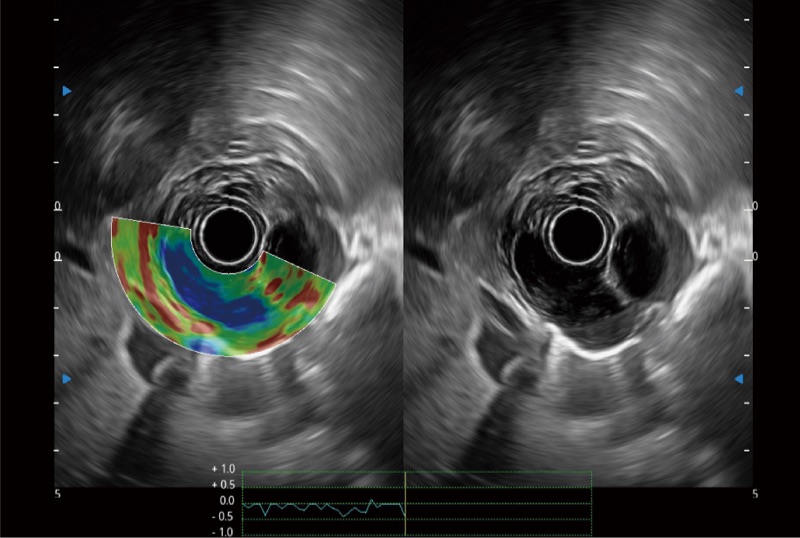

可人为将灰阶图像转变成彩色的显示方式,增强人眼对于不同回声强度的敏感度,主观上增加了图像分辨率

微米成像技术提升了对组织斑点噪声信号的抑制能力,并进一步强化边界信息,从而获得信噪比更优、边界更清楚锐利的图像

随着组织深度的变化,超声接收频率进行智能匹配跟踪,确保图像中、远场良好的穿透力以及整场一致的分辨力,从而得到均一的画质

位移矫正技术

不可靠区域自动剔除

弹性定量分析软件